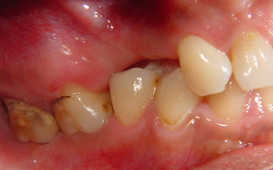

咬合崩塌 / 上牙下墜 / 下牙上長 / 前牙飆出 / 傾倒 / 蛀牙 / 牙周病缺牙未重建 - 臨床實例

上面的牙往下墜,下面的牙往上長,前面的牙往外飆 – 咬合崩塌牙周病,蛀牙;這些現象必然發生,時間越久,問題越大,而且除非藉由矯正及其他牙科治療,無法修正。

缺牙導致牙齒移位 - 臨床實例一